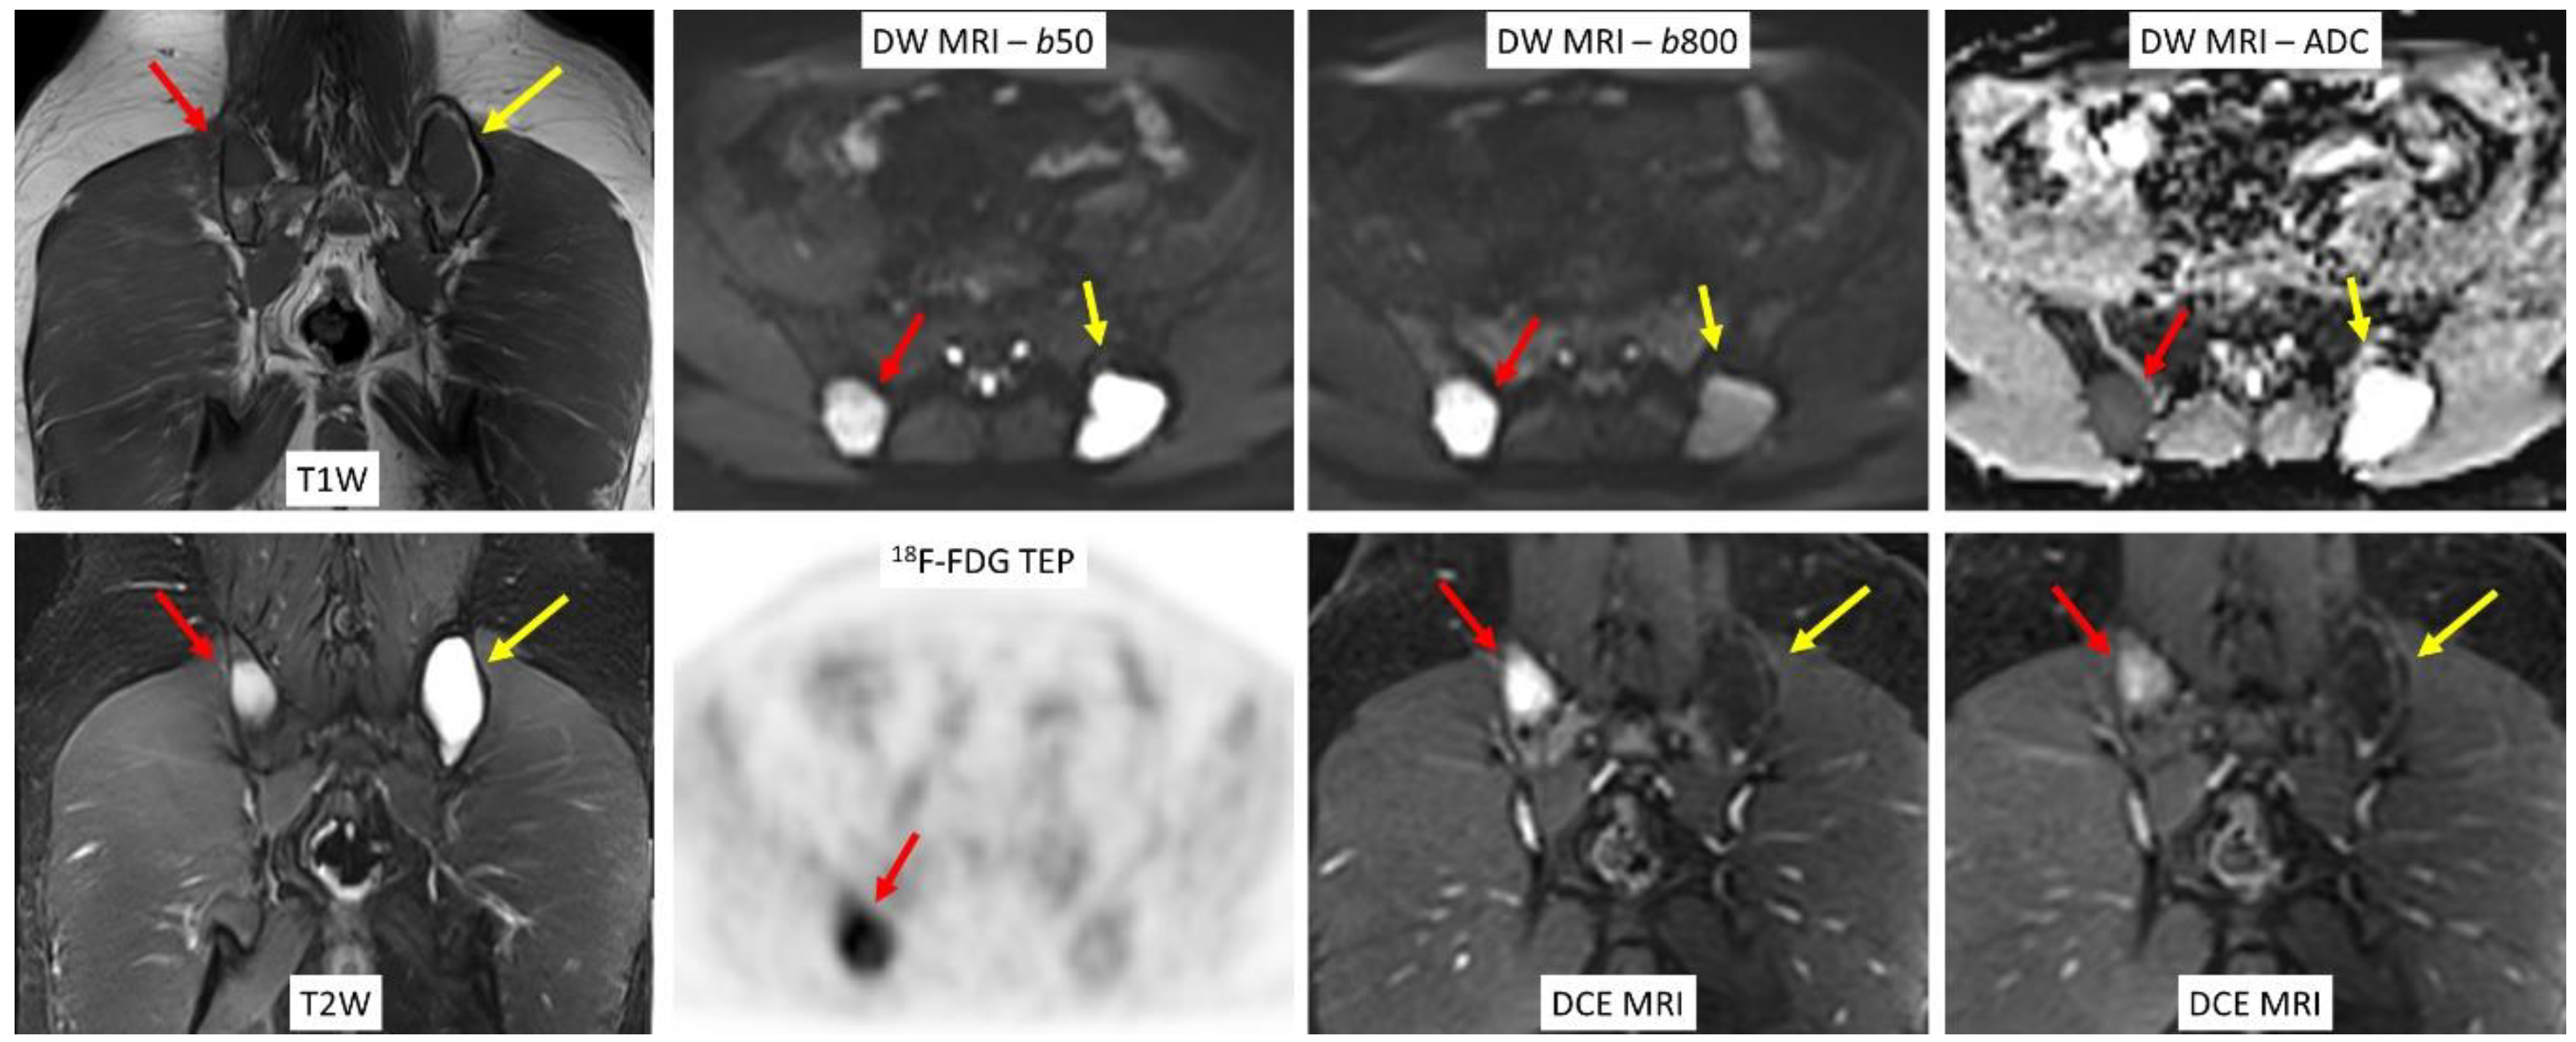

2.3. Whole-Body Diffusion-Weighted Imaging

2.4. Whole-Body Dynamic Contrast-Enhanced MRI

3. 18F-FDG PET/MRI